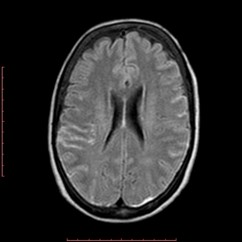

Discussão de tratamento de Fístula Arteriovenosa Dural grau I

Malformações artério venosas durais intracranianas - Discussão de caso fístula dural pós traumática grau I

Fístulas arteriovenosas durais (FAVDs) são lesões adquiridas, que consistem em uma ou mais conexões fistulosas no interior dos folhetos da dura-máter, envolvendo mais especificamente as paredes de um seio venoso dural ou as veias leptomeníngeas adjacentes.

O principal fator desencadeante do surgimento das FAVDs seria a hipertensão venosa. Condições trombóticas, como trombose do seio venoso, ou não trombóticas, como traumatismo craniano, podem promover restrição ao fluxo sanguíneo no interior do sistema venoso intracraniano, determinando elevação pressórica neste compartimento.  Propuseram que as FAVDs se desenvolvem por conta da abertura de pequenos canais vasculares (microshunts) existentes na dura-máter. Lawton et al ressaltaram que a hipoperfusão cerebral e a isquemia promovem angiogênese, levando ao desenvolvimento de novos shunts arteriovenosos.